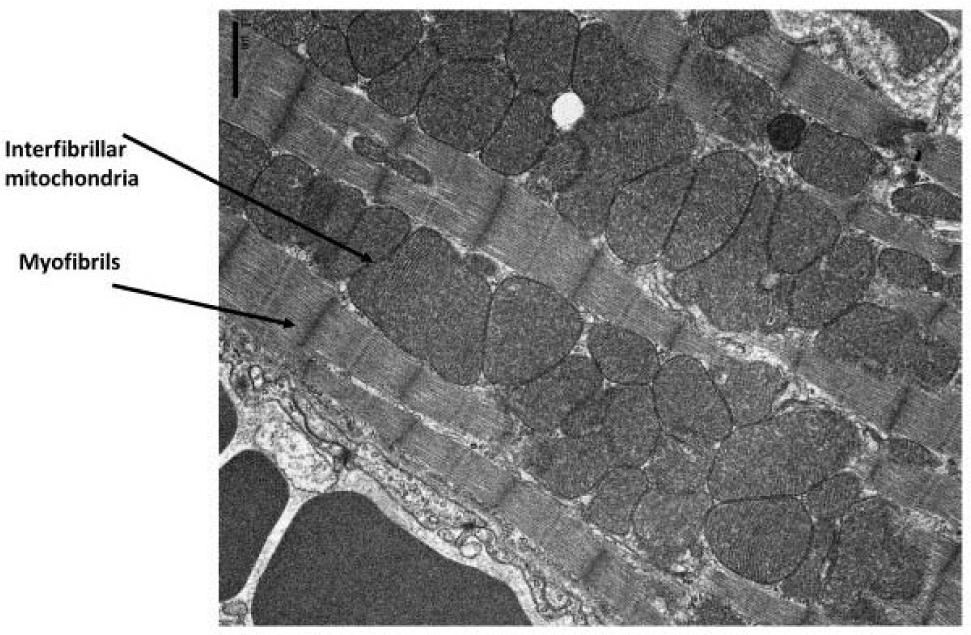

The heart weights only approximately 0.5% of the human body and consumes 8% of the 65 Kg of ATP produced by the whole body per day. Therefore, the heart is the highest metabolically active tissue in the human body. Approximately 95% of cardiac ATP results from mitochondrial oxidative metabolism with the rest deriving from glycolysis6. Cardiomyocytes are rich in mitochondria that are located both beneath the plasma membrane (subsarcolemmal) and within the interfibrillar regions of cardiomyocytes (Figure 2).

Figure 2

Electron microscopy image of the mouse heart.